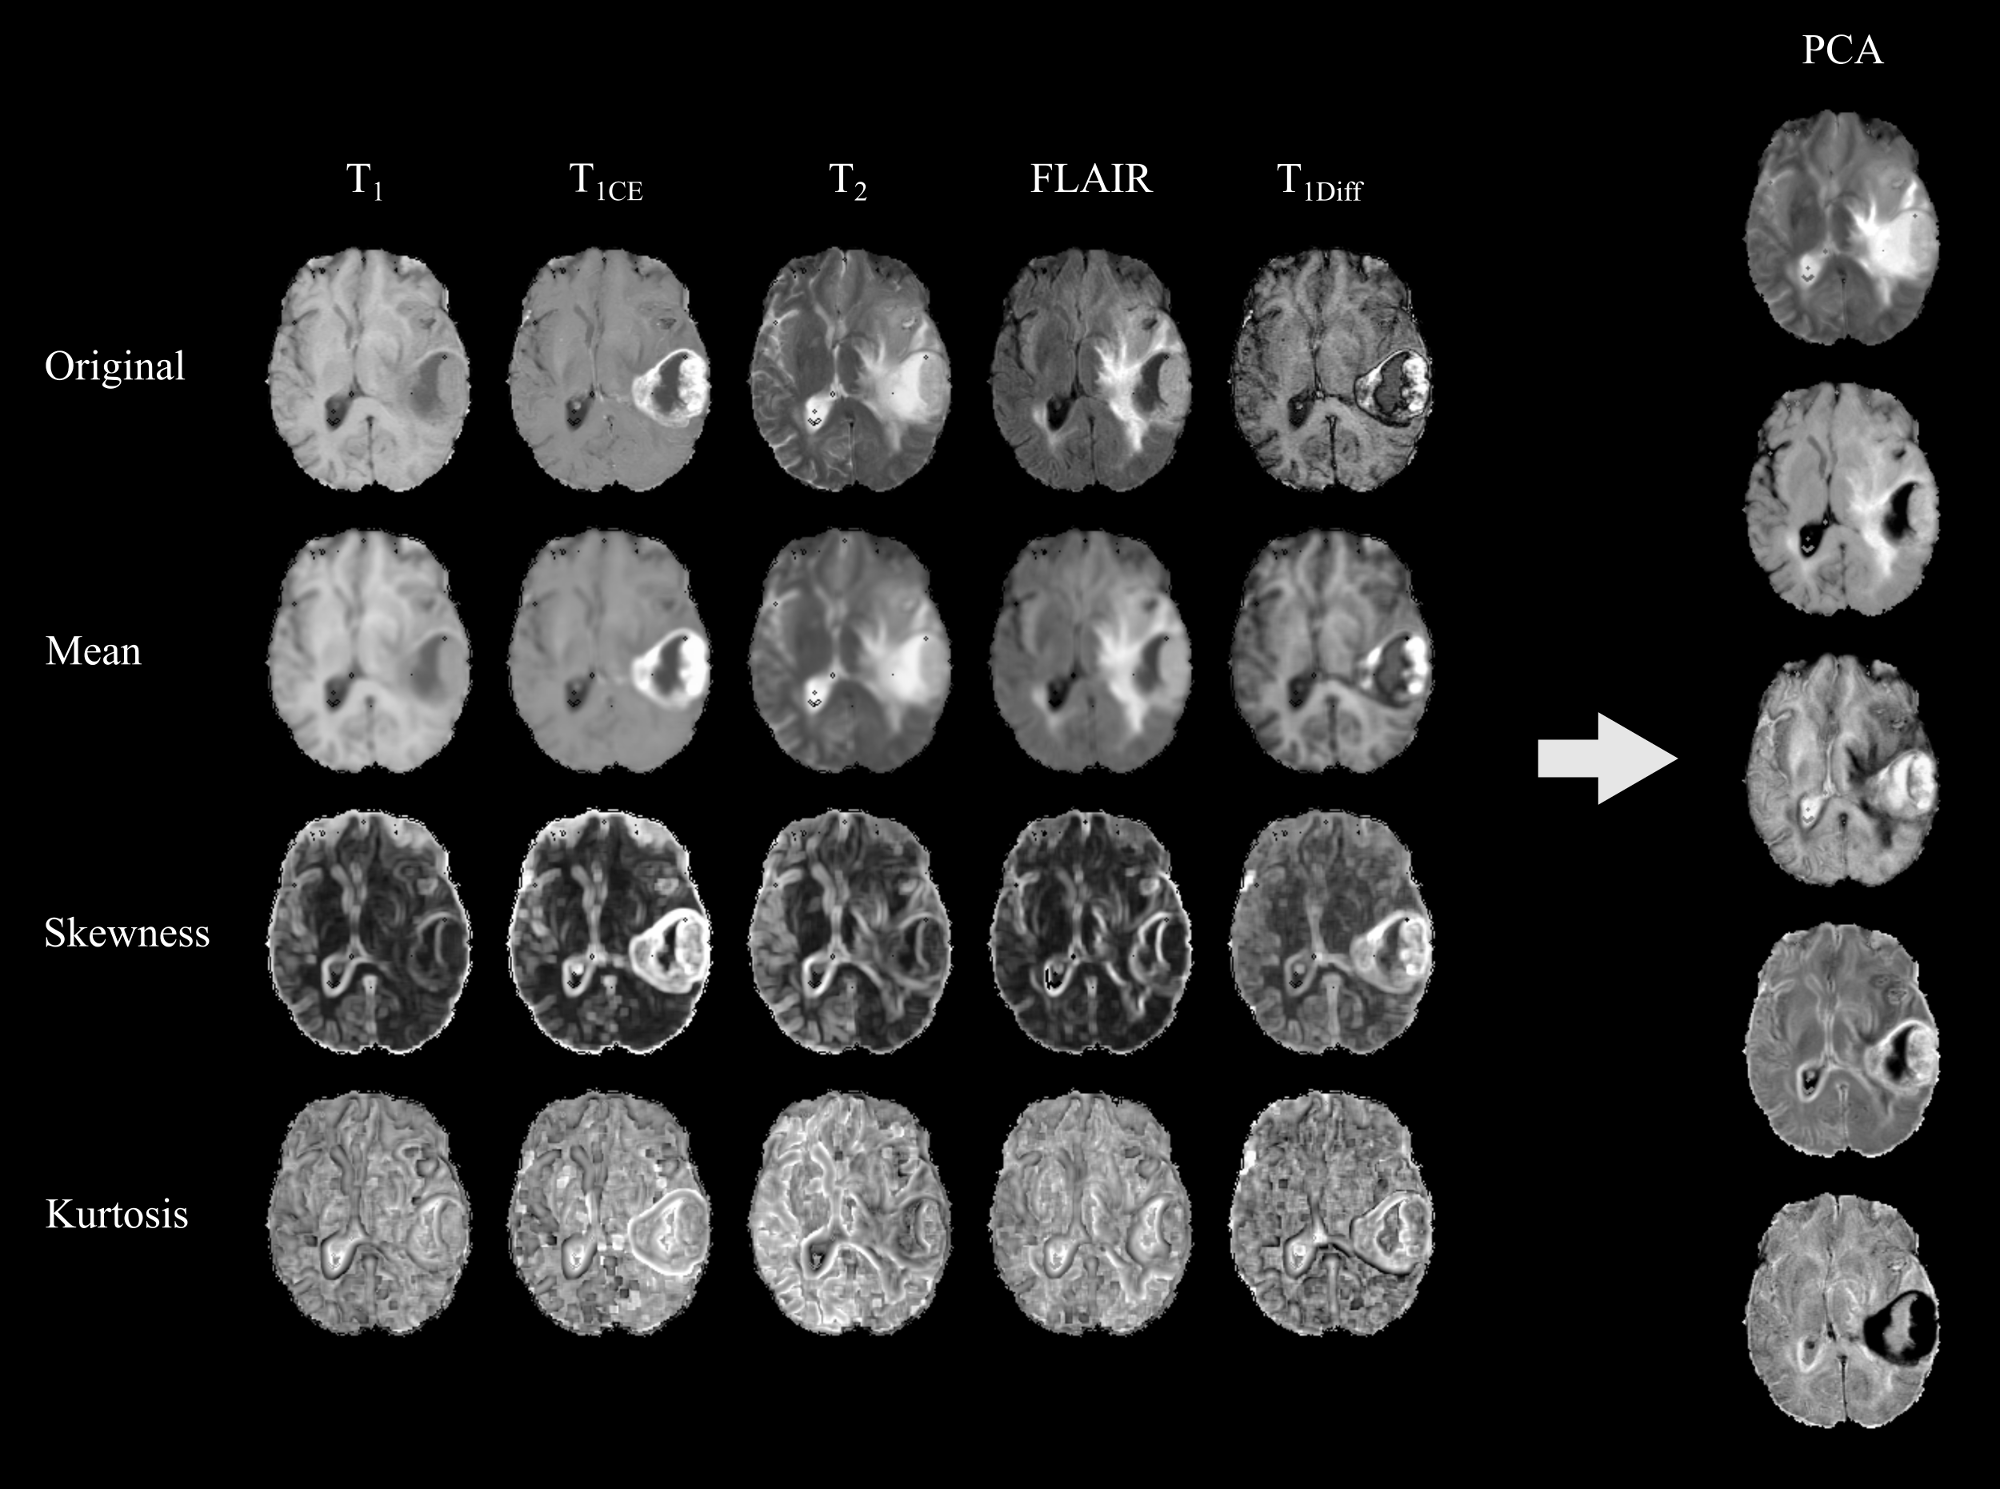

Comparative study of unsupervised learning algorithms for glioblastoma segmentation

In this study, a comparison of unsupervised learning algorithms, including structured and non-structured methods was performed for the task of high grade glioma segmentation. The study describes the statistical model underlying each algorithm and also proposes a general post-processing stage to identify which classes of an unsupervised segmentation correspond to pathological or healthy tissues. An independent evaluation of the performance of the unsupervised learning algorithms was carried out in a public real dataset, which demonstrated the capability of unsupervised learning to extract relevant knowledge from MRI data. This work was published in the journal contribution P1 (Juan-Albarracín et al, 2015b) and presented in the conference P2 (Juan-Albarracín et al, 2015a).